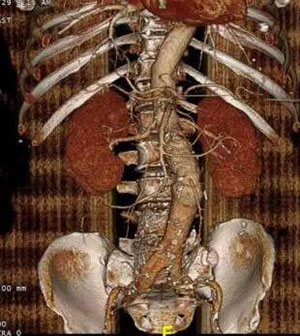

该患者为老年男性,腹主动脉瘤最大直径大于7cm(图1,图2),属于巨大腹主动脉瘤,如不及时处理,随时有发生破裂致猝死的可能。该患者既往高血压病史20余年,冠心病病史10余年,同时合并冠脉多支病变,脑梗塞病史2年,合并病多,不能耐受传统的开放手术,进行腹主动脉瘤切除+人工血管重建术;而该患者如行腔内治疗,近端肾下锚定区长度不足,传统情况下,此类患者一般会无法进行有效治疗,无奈等待破裂死亡。该患者曾于外院诊治,外院均无处理腹主动脉瘤的方法。

图2